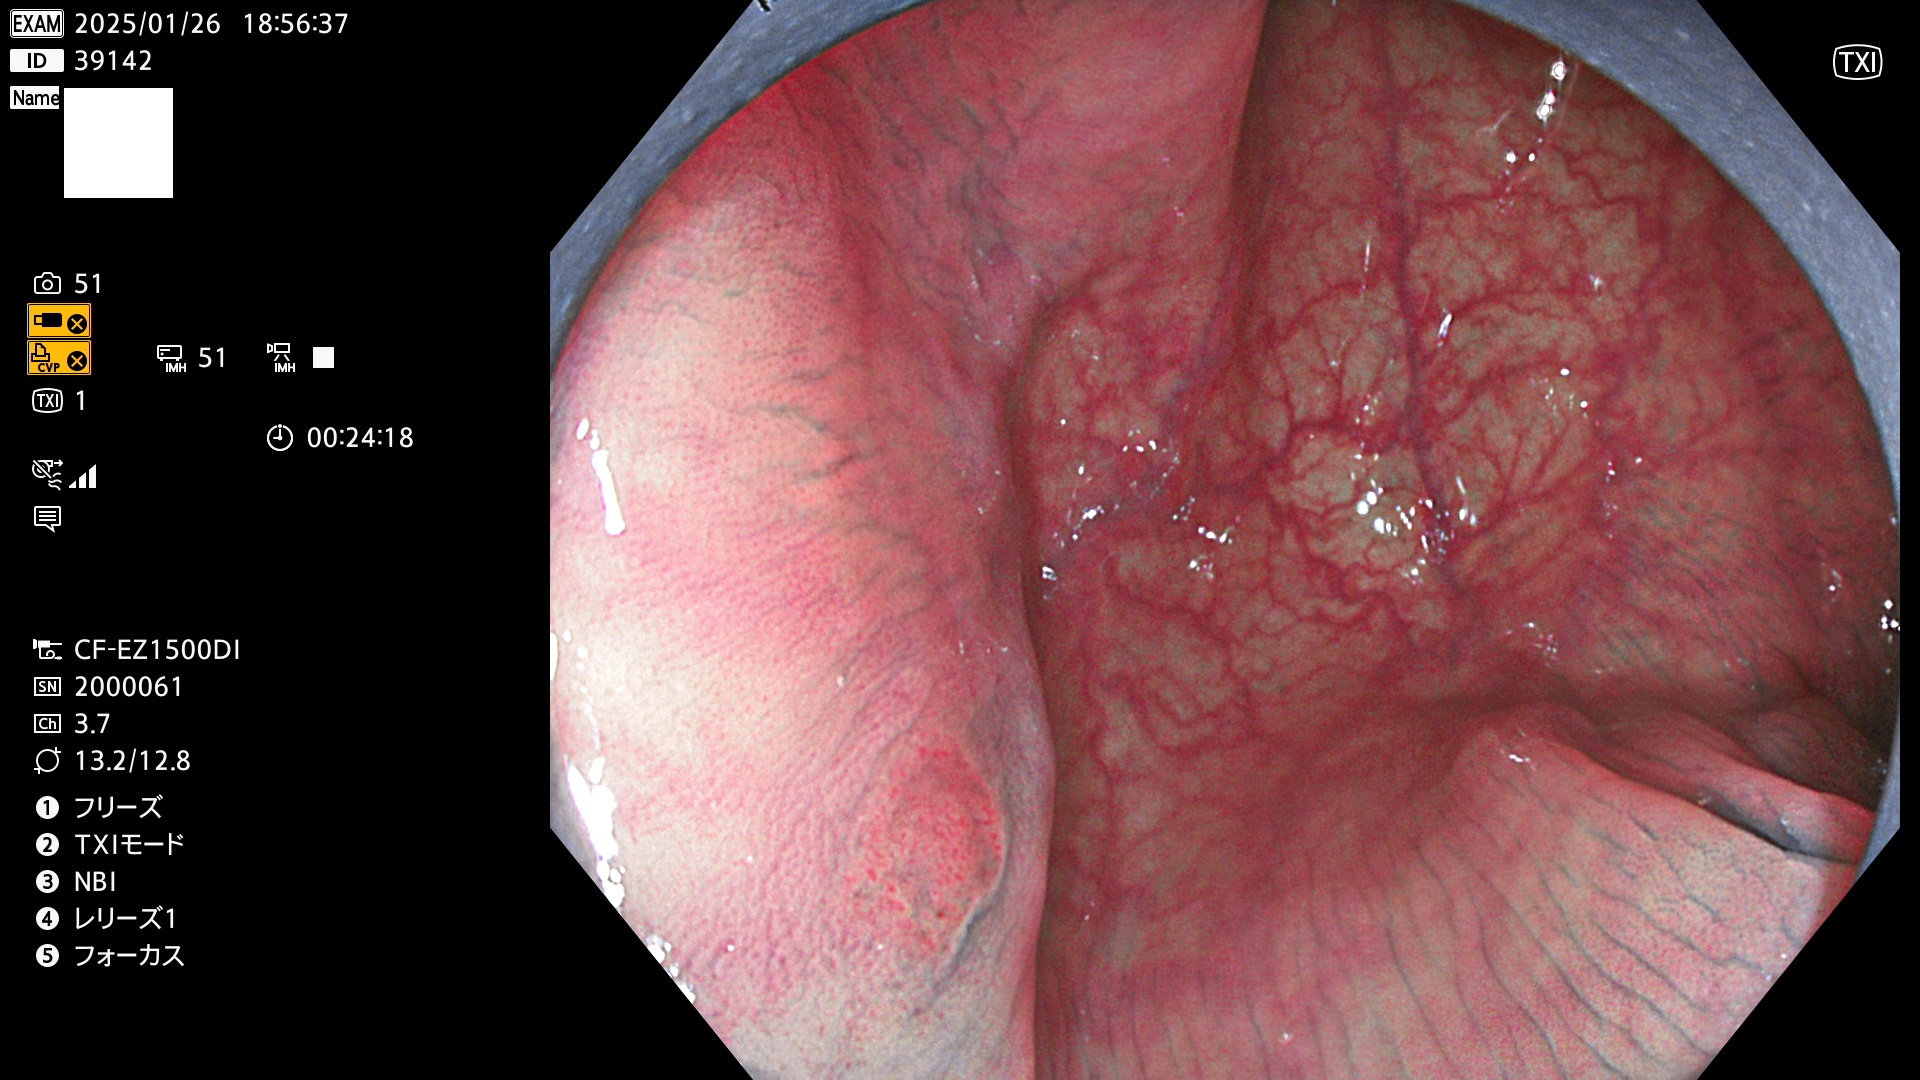

今週のUb、Uc型腺腫

完全に平坦な物をUb、陥凹している物をUcと呼びます。最も発見が難しく危険な病変です。

毎週の検査(木・金・土・日)に発見されたUb、Uc型・腺腫を、その週の日曜の夜にUPし1週間、提示します。

抽出の対象期間 2025年1月23日〜1月26日の4日間(45件の検査)3個 (3/45=6%)